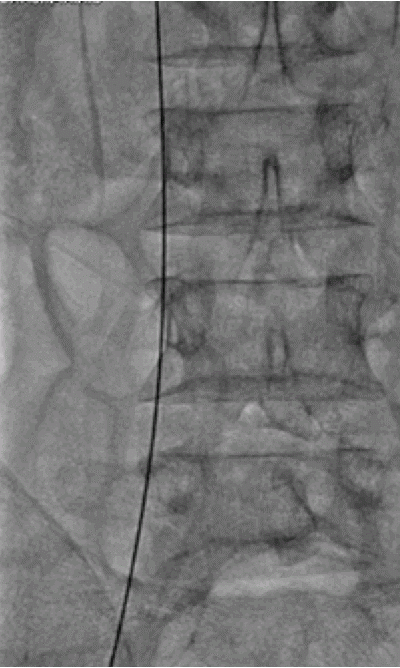

Basics and newer interventions with hands-on workshop